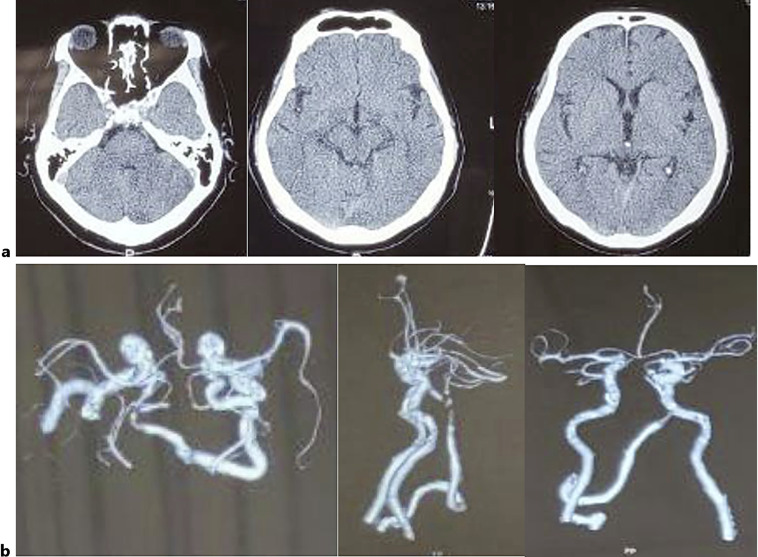

Case presentation: We present the case of a 64-year-old male diagnosed with basilar artery occlusion who underwent a successful mechanical thrombectomy 11 days after symptom onset. Despite complications such as hemorrhagic transformation and herniation, the patient was stabilized and showed functional improvement 3 months post-stroke.